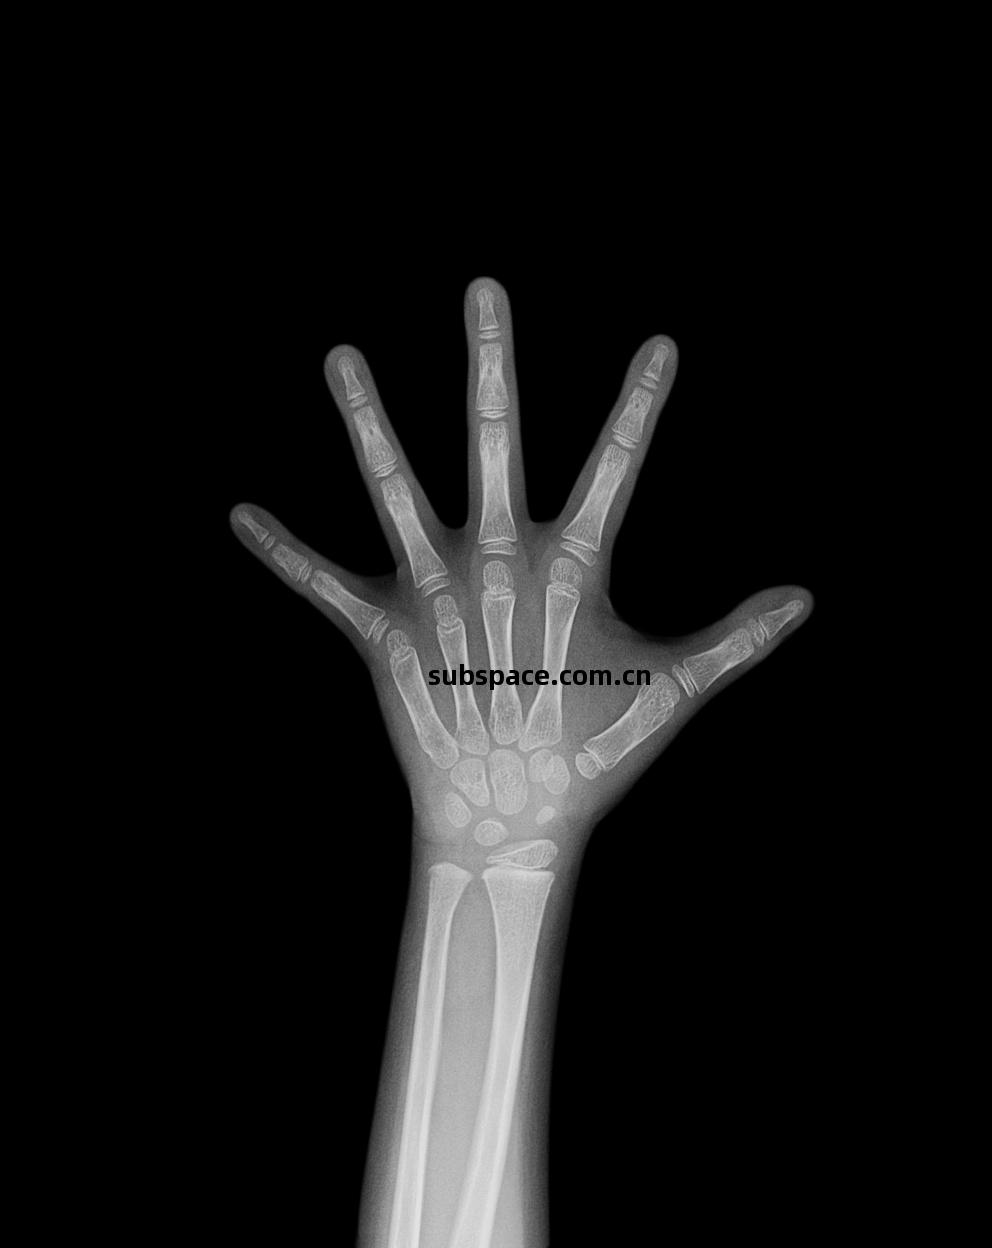

X射(she)線(xian)骨齡(ling)儀(yi)是(shi)利(li)用(yong)X射(she)線(xian)吸收成(cheng)像(xiang)法拍攝(she)手腕(wan)部的X射(she)線(xian)圖(tu)片,對照(zhao)圖(tu)譜進行(xing)骨(gu)齡(ling)等(deng)級(ji)判讀,從(cong)而得出(chu)骨(gu)齡(ling)結果,評估(gu)受檢者生(sheng)長(chang)發育(yu)情(qing)況的壹(yi)種設備。